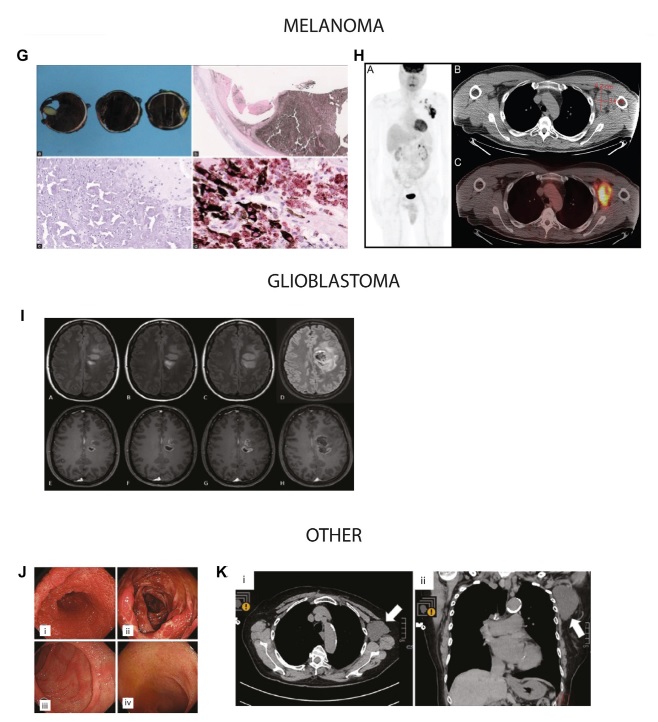

De beschreven kankertypen zijn divers. Het gaat onder meer om hematologische maligniteiten, zoals non-Hodgkinlymfomen, cutane lymfomen en leukemie, maar ook om solide tumoren, waaronder borst-, long-, pancreas- en huidkanker, sarcomen en glioblastomen. Over de verschillende publicaties heen signaleren de auteurs enkele terugkerende klinische patronen, waaronder een opvallend snelle tumorprogressie en herhaling of heractivatie van eerder stabiele ziektebeelden. Ook worden atypische histopathologische kenmerken genoemd, zoals afwijkingen nabij vaccinatieplaatsen of regionale lymfeklieren.